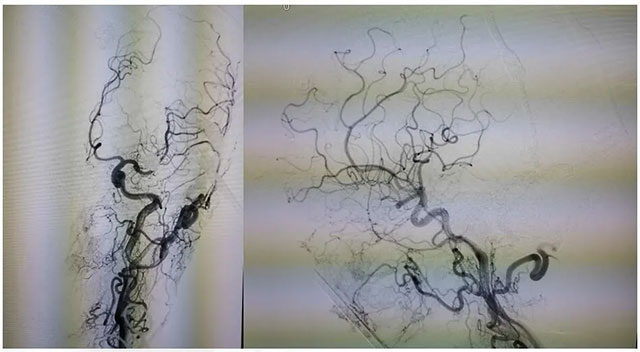

▲ 术后影像

术后患者临床症状消除,精神矍铄,现正在康复中。